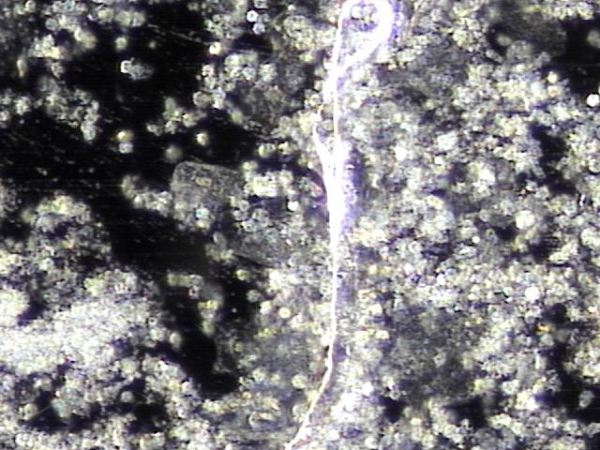

주 1회 전립선의 표적 치료중이라도 하루 약 300만 마리의 정자가 고환에서 생산되어 사정관이 막혀 정자의 순환 장애로 정낭에 모여 혈정액 혹은 정낭 결석과 하복부 통증 그리고 만성 골반통 증후군등의

원인의 치료된 현미경학적 자료입니다.

Even though the testes naturally produce about 3 million sperm every day, blockages in the ejaculatory ducts can sometimes prevent sperm from flowing properly. This can cause semen to build up in the seminal vesicles, leading to blood in the semen, stones, lower abdominal pain, or chronic pelvic pain. Thanks to the targeted treatments, these blockages are being cleared, and this microscopic image shows the tissue after successful treatment.